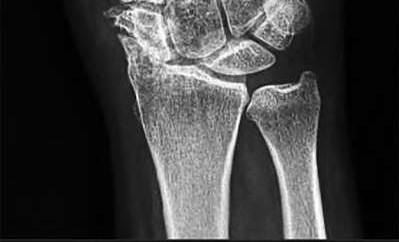

A 35-year-old woman reports wrist pain after a fall onto an outstretched hand. On exam, she has focal tenderness over the wrist snuffbox. A radiograph and CT image are shown in Figures A and B. What is the proper treatment of her injury?